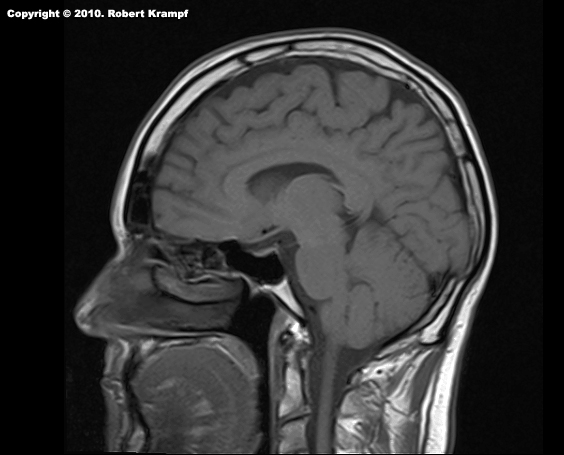

This is a shot from the MRI series of my brain. What does MRI stand for, and how do they work?

MRI stands for Magnetic Resonance Imaging. To produce the images, a person is placed inside a very powerful electromagnet. When the magnet is turned on, the magnetic field is strong enough to cause the protons in hydrogen atoms to align with the magnetic field.

Since the human body is mostly water, it has lots of hydrogen atoms. When the magnet is turned off, the hydrogen atoms return to their previous alignment, giving off energy in the form of radio waves.

That radio signal is picked up by sensors. Different tissues have different amounts of water, so the signal varies from one tissue to another. That makes the MRI very useful in seeing different types of tissue, as well as abnormalities such as tumors.